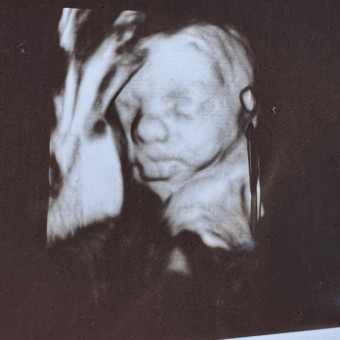

Baby Registry for Mary Charles 💕

Thank you so much for visiting our baby registry! We’re excited to welcome baby girl and grateful for your love and support as we start this new chapter of a family of 4!